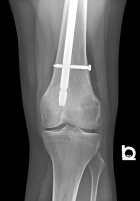

Patient is a 26 y/o male w/ hx. of polyostotic fibrous dysplasia s/p IM nailing for a pathologic L. femur fx. seven yrs. ago presents c/o 1 yr. hx. of increasing L. lat knee pain/swelling; PMH: polyostotic fibrous dysplasia and L. humerus fx; PE: L. knee w/ minimal effusion; +TTP over lat. condyle and w/ flexion to 100 deg; NVI